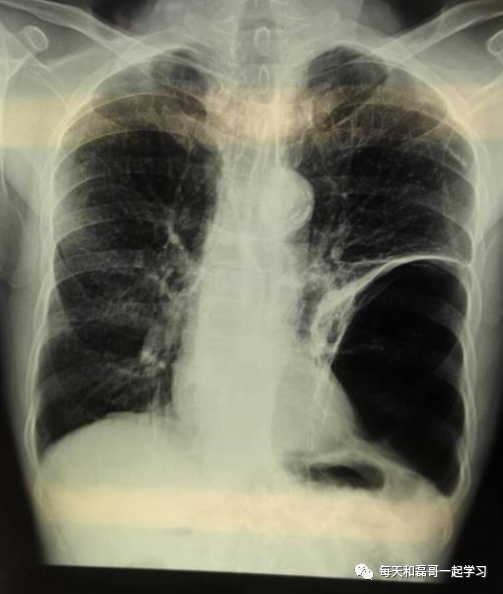

(3)伴肺大疱的呼吸衰竭

肺大疱患者接受机械通气时,大疱内压力可升高而引起大疱破裂,引起张力性气胸。这类患者使用呼吸机时应注意患者肺大疱的程度、范围及是否有气胸病史,正压通气的压力应尽可能低,而且在机械通气过程中,应密切注意观察患者生命体征和肺部体征,以防发生气胸。一旦发生气胸,应立即进行胸腔闭式引流。